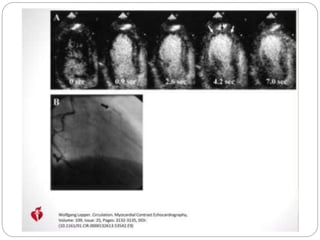

Contrast Echocardiography

 Myocardial contrast echocardiography (MCE)

evaluates myocardial microvascular integrity

 Viable myocardium has preserved microvascular

integrity

 Intravenously injected bubble contrast agents lead

to contrast enhancement of dyssynergic but viable

myocardial segments that can be detected with

echocardiography

 Non-viable myocardium does not show significant

enhancement with bubble contrast due to disruption

of the coronary microvasculature.